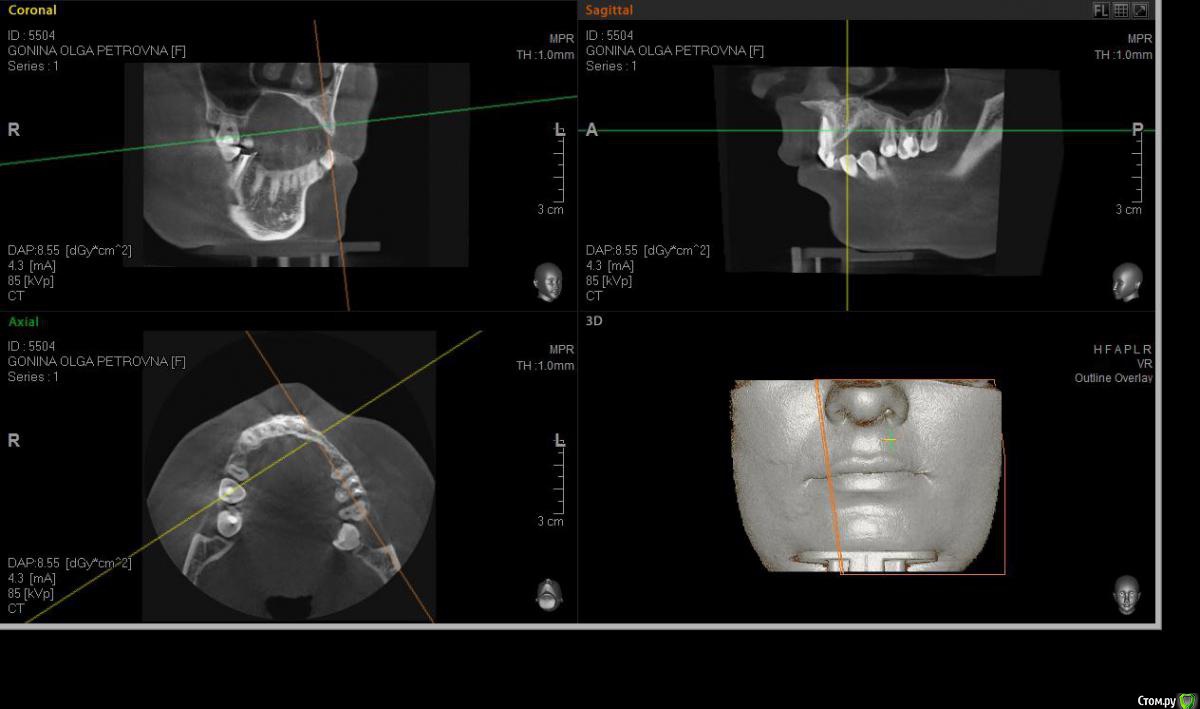

denis1987 Опубликовано 6 декабря, 2014 Поделиться Опубликовано 6 декабря, 2014 Здравствуйте, коллеги. У пациентки частичная вторичная адентия на верхней челюсти слева, отсутствующие зубы 22,23,24. С ортопедом запланировали имплантацию. Снимки прилагаю. Форма альвеолярного гребня вроде как то не особо располагает для расщепления, но все таки хочу попробовать. За ответы заранее спасибо. Ссылка на комментарий